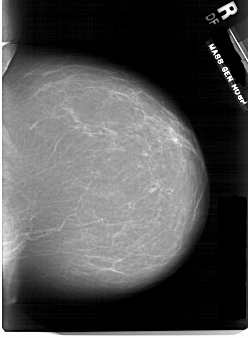

Жирная (не плотная) грудь

Умеренно плотная грудь

Плотная грудь

Маммограммы представляют собой изображения структур, проецируемых на плоскость: плотная грудная маммограмма, следовательно, состоит из многих других структур, которые необходимо проанализировать, чем более жирная, пустая грудь. По этой причине диагностировать рак молочной железы труднее для моложе, чем для пожилых женщин.

Нажмите на миниатюрные картинки, чтобы получить увеличенный размер.